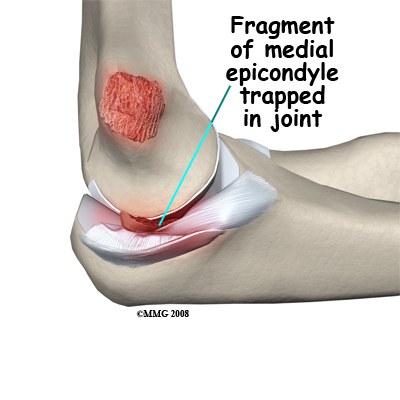

Avulsion of the medial epicondyle: The medial epicondyle is the origin site of the strong medial collateral ligament of the elbow and the flexor muscles of the forearm. A force that bends the elbow outwards may dislocate it and disrupt the ligaments on the inner side of the elbow. This may result in an avulsion (pull-off) fracture of the medial epicondyle. The medial collateral ligament pulls off a fragment of the bone.

As the elbow may be opened up widely in such an injury, the piece of bone broken off may end up trapped inside the joint. In this case it is necessary to do an operation to extract the bone fragment from the joint and fix it back into place. More commonly the avulsed piece of bone is still close to its correct position and the injury can be treated non-operatively. Avulsion of the medial epicondyle as a result of a muscle pull is rare. This injury can usually be treated without surgery.

Displaced avulsion fractures. Fractures of the epicondyles and the coronoid process are usually avulsion fractures. This means that the piece of bone was pulled off by a muscle or ligament. Usually, the fracture fragment is still being pulled away from the correct position after the injury. This may prevent the bone from healing back to the correct location when it is immobilized. If the bone fragment is not in an adequate position for healing, it should be replaced and fixed by surgery.

In the case of a medial epicondyle fracture, the bone fragment is sometimes trapped in the elbow joint. The joint must be opened up and explored to remove the fragment(s). If these injuries are part of a more complex combined injury, there is even more reason to fix them back into position. After stable fixation of these fragments, the elbow can more safely be moved to prevent stiffness. Activity should be guarded until the bone has healed. Olecranon Fractures. The fragments of this fracture are nearly always pulled apart by the pull of the triceps muscle. Surgery is indicated to restore the joint surface accurately and to fix the fracture in the reduced position. The olecranon process is just under the skin and easily exposed surgically. The fracture is often held in position by pins and a figure-of-eight wire.